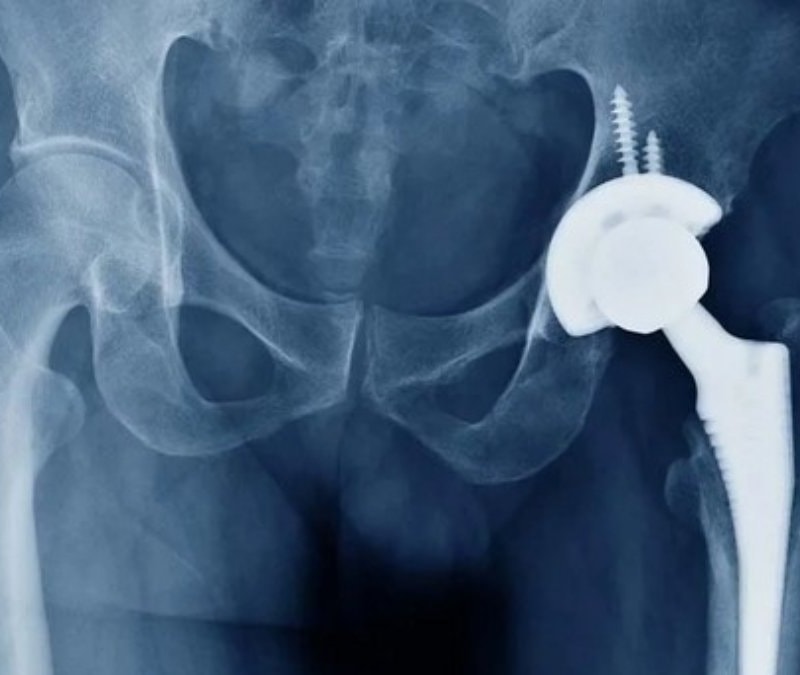

Ortopedi alanında geliştirilen yeni cerrahi alet, kalça protezi ameliyatlarında görüş alanını açık tutarak operasyonu daha güvenli ve kontrollü hale getirmeyi hedefliyor.